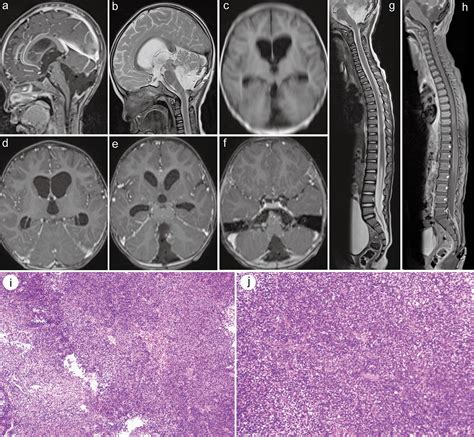

Diagnosis typically begins with advanced neuroimaging, such as MRI scans with and without contrast, to visualize the tumor's size and location. However, imaging alone is rarely sufficient. A definitive diagnosis is achieved through a surgical biopsy or total resection, followed by a rigorous pathological examination. Pathologists look for the loss of INI1 protein expression in the tumor cells, which serves as a molecular hallmark for an Atypical Teratoid Tumor.

• Atypical Teratoid Rhabdoid Tumor Histology

• Atypical Teratoid Rhabdoid Tumor MRI